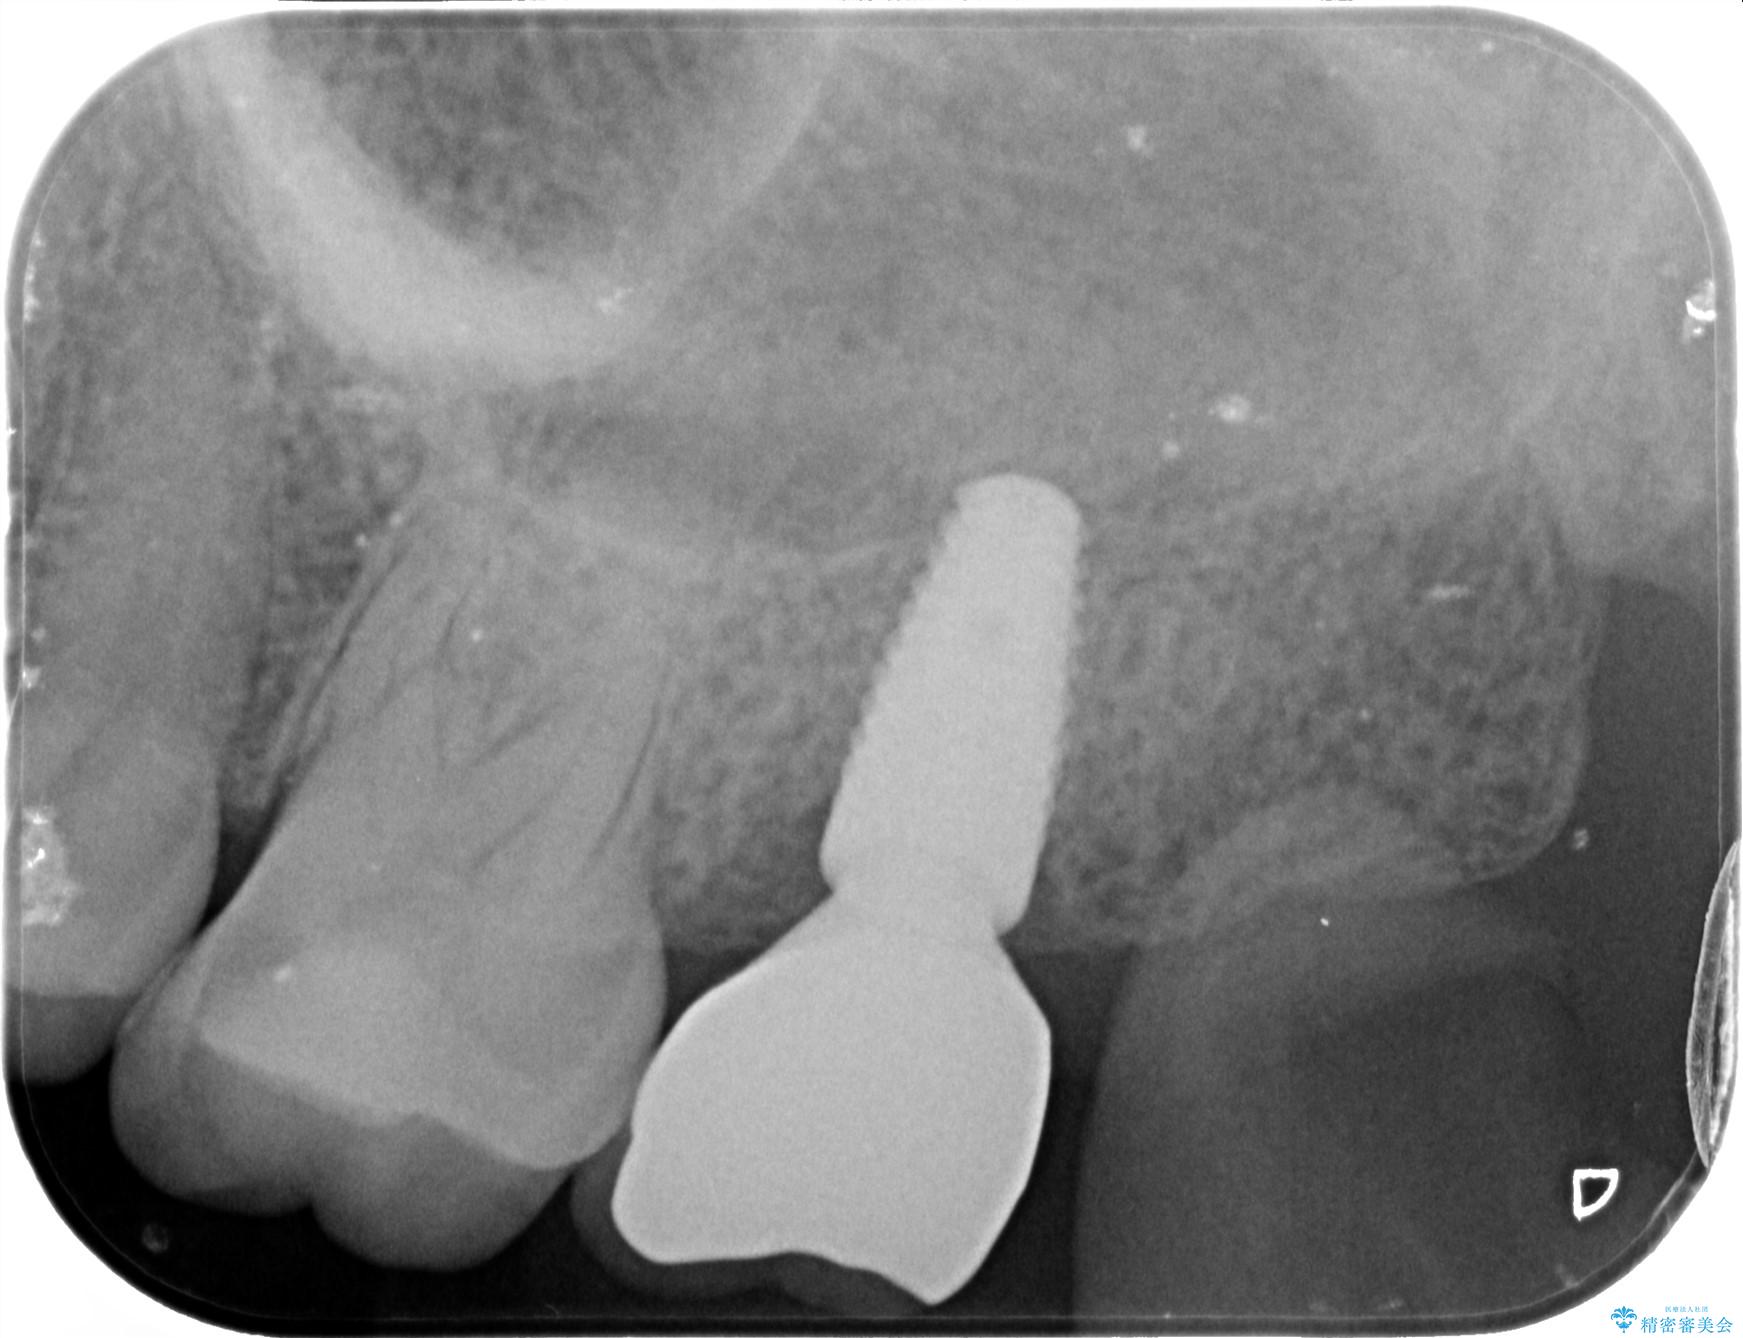

歯の抜去後、しっかりと咬合機能を回復するためインプラントを用いた治療を行っていきます。

治療中

【噛むと歯が疼く】歯牙破折からのインプラント治療 治療中画像 【噛むと歯が疼く】歯牙破折からのインプラント治療 治療中画像 【噛むと歯が疼く】歯牙破折からのインプラント治療 治療中画像 【噛むと歯が疼く】歯牙破折からのインプラント治療 治療中画像